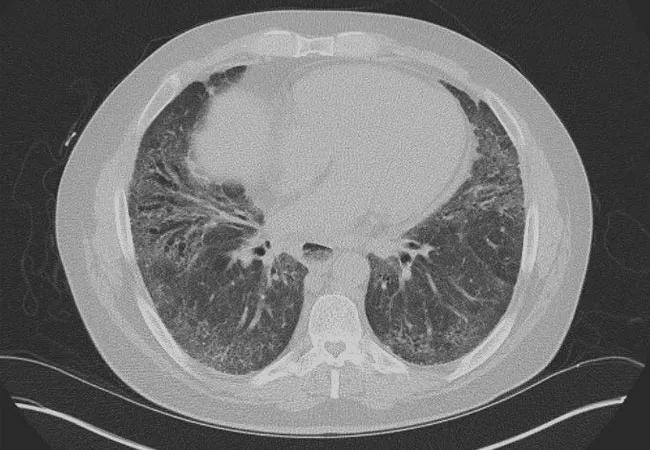

Exploring Novel Treatment for Scleroderma-Associated Interstitial Lung Disease

Systemic sclerosis (SSc) is a debilitating disease of unknown etiology. Patients suffer from fibrosis of multiple organs, leading to chronic morbidity and premature death. Second only to skin involvement, lung involvement is common and portends a poor prognosis, with a median survival of five to eight years in SSc-ILD.

Nintedanib is an antifibrotic agent that is approved for the treatment of idiopathic pulmonary fibrosis based on its ability to slow the rate of decline in FVC. In animal models of SSc, nintedanib effectively attenuated skin and lung fibrosis by reducing extracellular matrix deposition and myofibroblast accumulation. Nintedanib also attenuated pulmonary vascular remodeling by reducing the number of vascular smooth muscle cells and occluded pulmonary vessels. Lastly, nintedanib has been demonstrated to inhibit T-cell and B-cell activity. These pleiotropic effects of nintedanib on the fibrotic, vascular and inflammatory pathways support its further investigation in rheumatic lung disease.

The SENSCIS® study, which I colead with Dr. Oliver Distler of the University Hospital in Zurich, Switzerland, is a multinational, randomized, placebo-controlled trial of nintedanib versus placebo in 580 subjects with SSc-ILD, making it the largest trial in scleroderma to date. Patients may be on baseline MMF or methotrexate. The primary outcome measure of the trial is the annual rate of decline in FVC over 52 weeks, while secondary measures are skin fibrosis score and quality of life as measured by the Saint George’s Respiratory Questionnaire.